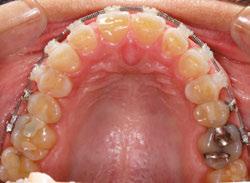

The orthodontic treatment plan was to bond upper and lower Ormco Symetri brackets (bidimensional prescription) and intrude teeth Nos. 7-10 along with lower anterior (teeth Nos. 23-26) to establish better overbite and overjet for restorative work. Due to the loss of height of her anterior teeth, the interproximal contacts had also moved gingivally, which decreased the width of the anterior teeth (height-to-width ratios were off). In order to establish better crown ratios, the

plan was to open space mesial and distal to teeth Nos. 7-10 with open coil springs.

Though she had a rather deep bite, the Ormco Symetri bracket was low-profile and petite enough to bond the entire upper and lower braces the same day. She had no occlusal interferences with the brackets, and bite turbos were not required. The Symetri bracket’s rounded contours were comfortable to the patient, and she liked that the brackets blended with her tooth shade and met her esthetic requirements. She reported adjusting to the braces easily. The initial wires were light, 0.014 nickel-titanium archwires, and we gradually progressed into rectangular, 0.16 x 0.22 stainless steel wires for finishing. Coils were added mesial and distal to teeth Nos. 7-10 to improve the width-tolength ratios of the crowns, and teeth Nos. 7-10 were stepped up gradually to intrude them. Ideally, gingival margins of teeth Nos. 8 and 9 should be at the level of tooth No. 6 and 11, while teeth Nos. 7 and 10 should be about 1.5 mm lower5 than the centrals. As the maxillary anterior teeth were intruded, and spaces were introduced mesial and distal, the incisal angulation of the teeth also increased. This can be protective for people with a history of bruxing, in addition to leaving more inter-incisal clearance for the restoring dentist.

Figures 7-10: Images with braces, with and without coils, facial and maxillary occlusal views